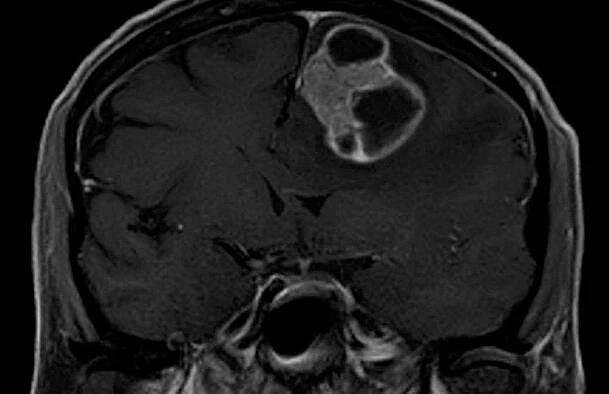

Funkční anatomie a neurologické projevy mozkových metastáz

Mozkové metastázy jsou častou komplikací systémových nádorových onemocnění, z nichž 60–75 % se v průběhu života stává symptomatickými.